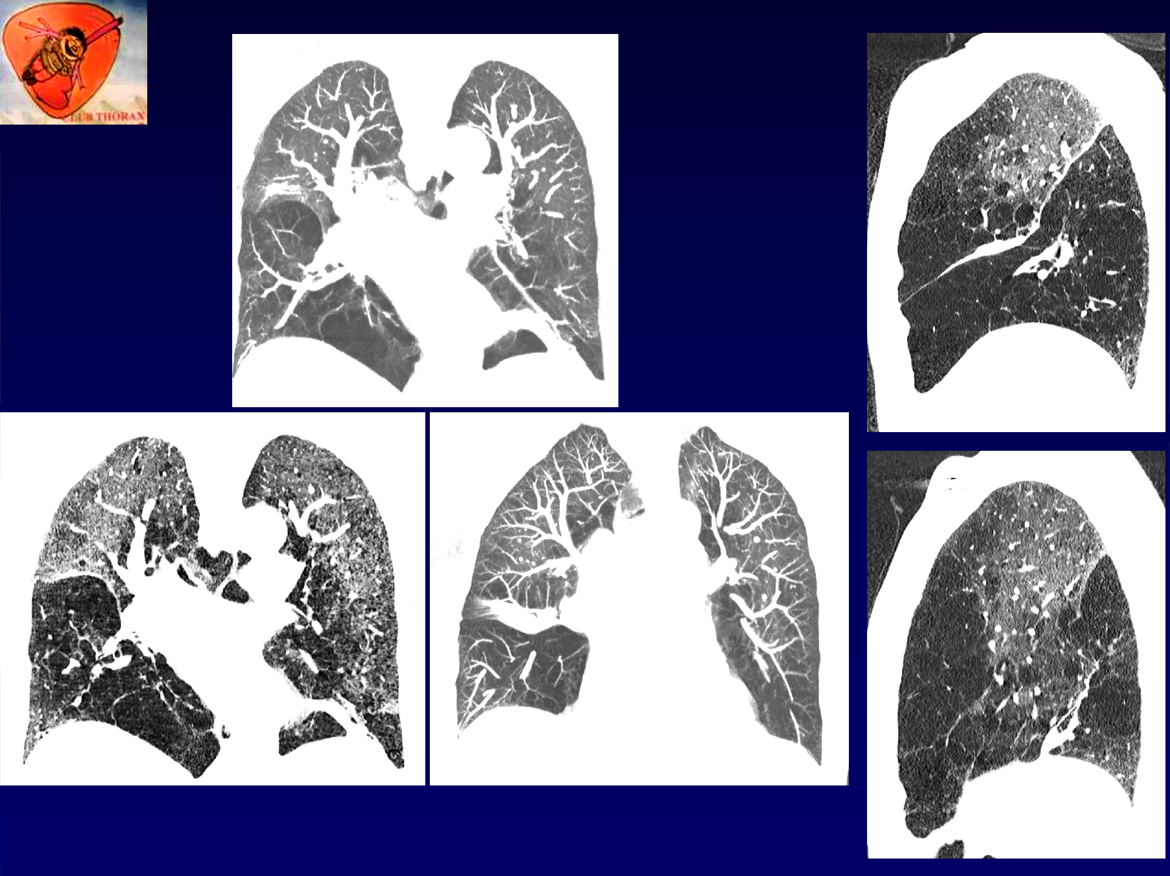

Femme , 76 ans, non tabagique

ATCD: PR traitée depuis 4 ans par du plaquenil, problèmes respiratoires dans l’enfance et dans la famille, asthme depuis 35 ans. Mélanome dorsal opéré à 2 reprises (2022).

Examen: thorax distendu, MV aboli.

RT: hyperclarté , distension, gracilité vasculaire des LI.

EFR:

Tiffeneau = 28%

VEMS 30% (0,5L)

VR 3,5 L (159%)

Désaturation effort++